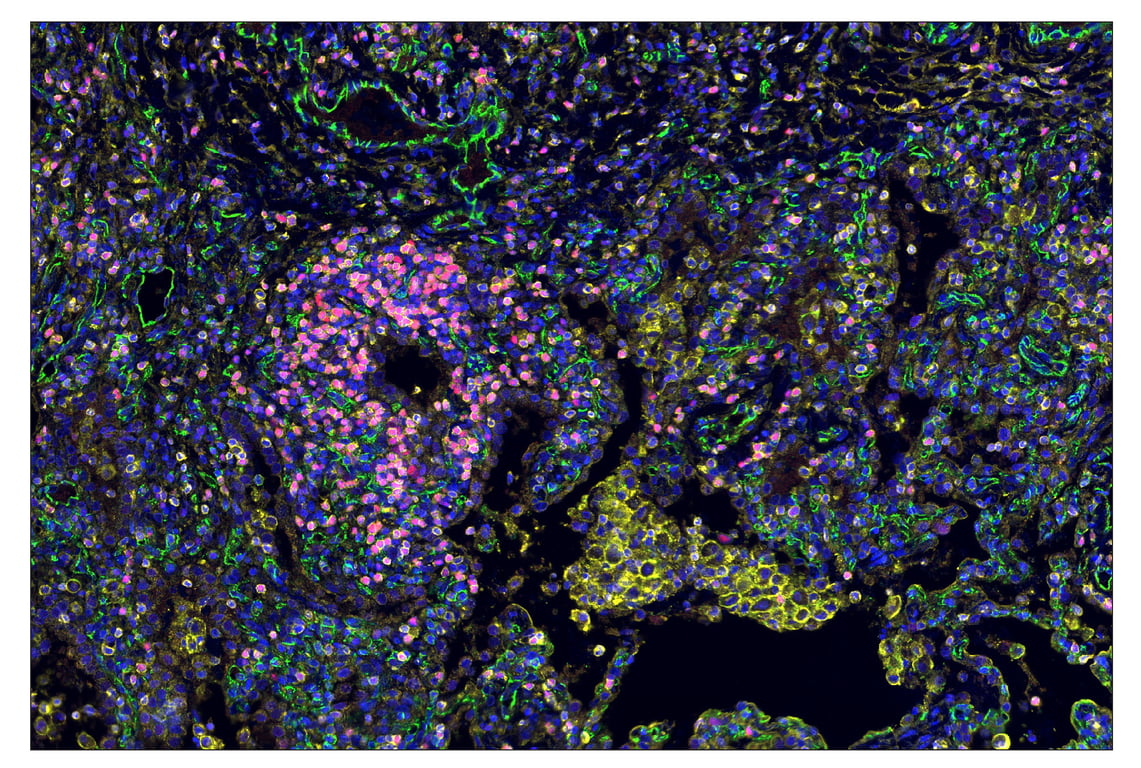

SignalStar™ multiplex immunohistochemical analysis of paraffin-embedded human tonsil using TIM-3 (D5D5R™) & CO-0010-647 SignalStar™ Oligo-Antibody Pair #15231 (red), PD-L1 (E1L3N®) & CO-0005-488 SignalStar™ Oligo-Antibody Pair #85646 (green), PD-1 (Intracellular Domain) (D4W2J) & CO-0008-594 SignalStar™ Oligo-Antibody Pair #35347 (yellow), Tox/Tox2 (E6I3Q) & CO-0016-750 SignalStar™ Oligo-Antibody Pair #81643 (cyan), CD3ε (D7A6E™) & CO-0001-488 SignalStar™ Oligo-Antibody Pair #92856 (pink), CD8α (D8A8Y) & CO-0004-594 SignalStar™ Oligo-Antibody Pair #19166 (orange), LAG3 (D2G4O™) & CO-0026-647 SignalStar™ Oligo-Antibody Pair #40966 (magenta), Pan-Keratin (C11) & CO-0003-750 SignalStar™ Oligo-Antibody Pair #97227 (white), and ProLong Gold Antifade Reagent with DAPI #8961 (blue). All fluorophores have been assigned a pseudocolor, as indicated. Staining was performed on the BOND RX by Leica Biosystems.

Immunohistochemistry Image 1: TIM-3 (D5D5R<sup>™</sup>) & CO-0010-750 SignalStar<sup>™</sup> Oligo-Antibody Pair